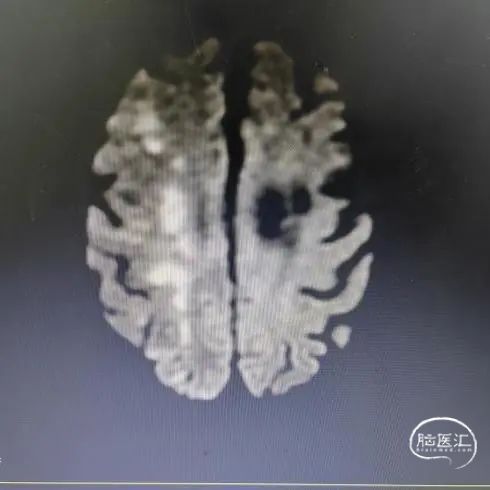

头颅DWI

头颅MRA